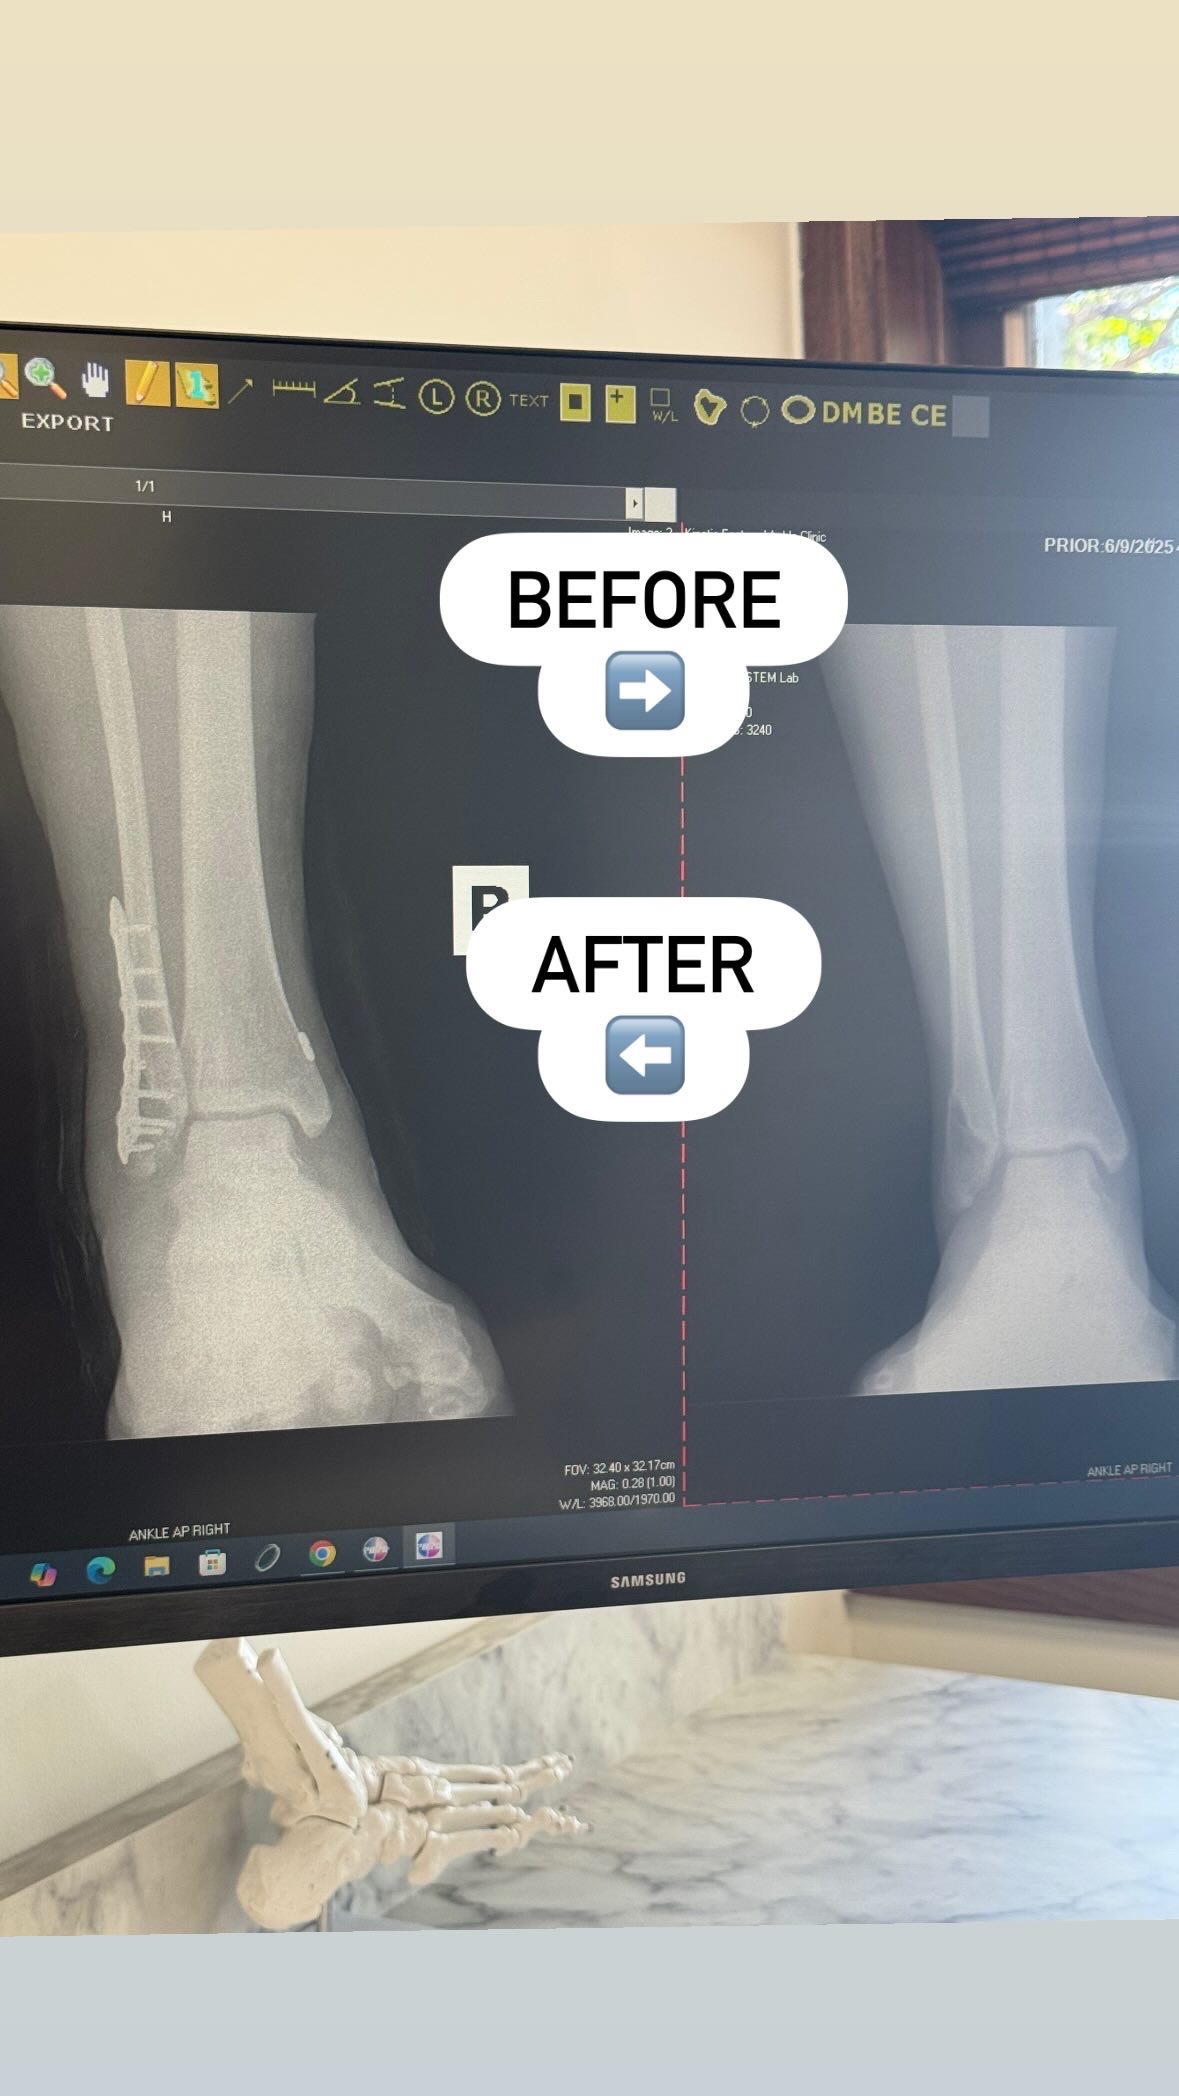

UPDATE: Surgery went well! Healing timeframe is currently set at about 3 months. Donations would go towards cost of rent, Uber since I can’t drive, and grocery delivery. Thank you so much for your love and support!!!

UPDATE: Surgery scheduled for July 8.

New findings-SEVEN ligaments in my ankle are torn. The bone will need re-broken, repaired and replaced. All ligaments

will need repaired. A scope will need done. 3 incisions.

I won't be walking again for 6 weeks, but hopefully this will fast track my healing and I'll be back in action in about 3-4 months.